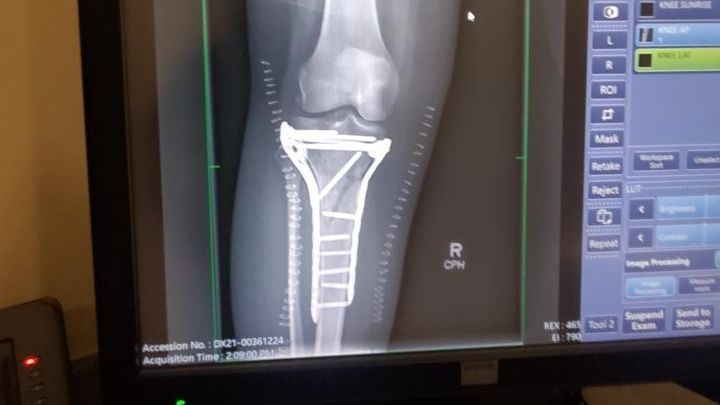

Surgery was needed to reset the bones and straighten my leg. I was put into an external fixation where they screwed this device into my bones to help me keep the bones in place while the swelling went down in my leg. This device was only supposed to be on for two weeks. At the follow-up to schedule the second surgery, the swelling had not gone down enough to put the plates and screws that would replace the external fixation. I was lucky that the fracture was not an open one and I was lucky to keep my leg because of how close the break was to my knee and how serious the fracture was to both bones.

I was in the external fixation for 3 weeks. Then I underwent the second surgery for the plates and screws. The surgery was supposed to be only 4 hours and it took almost 8 hours. According to the CT scan before the first surgery, the tibia bone had five fragments, however they found more during the surgery. I still could not put weight on my leg after the surgery. I was cleared for weight bearing at the beginning of November and had to learn how to walk again. I also had to retrain my brain to recognize my right leg again. I met my goal of walking with a cane before Christmas. I still have a limp and a long way to go before I am “100%” normal. The doctors think that I might not be 100%, but pretty close to it.